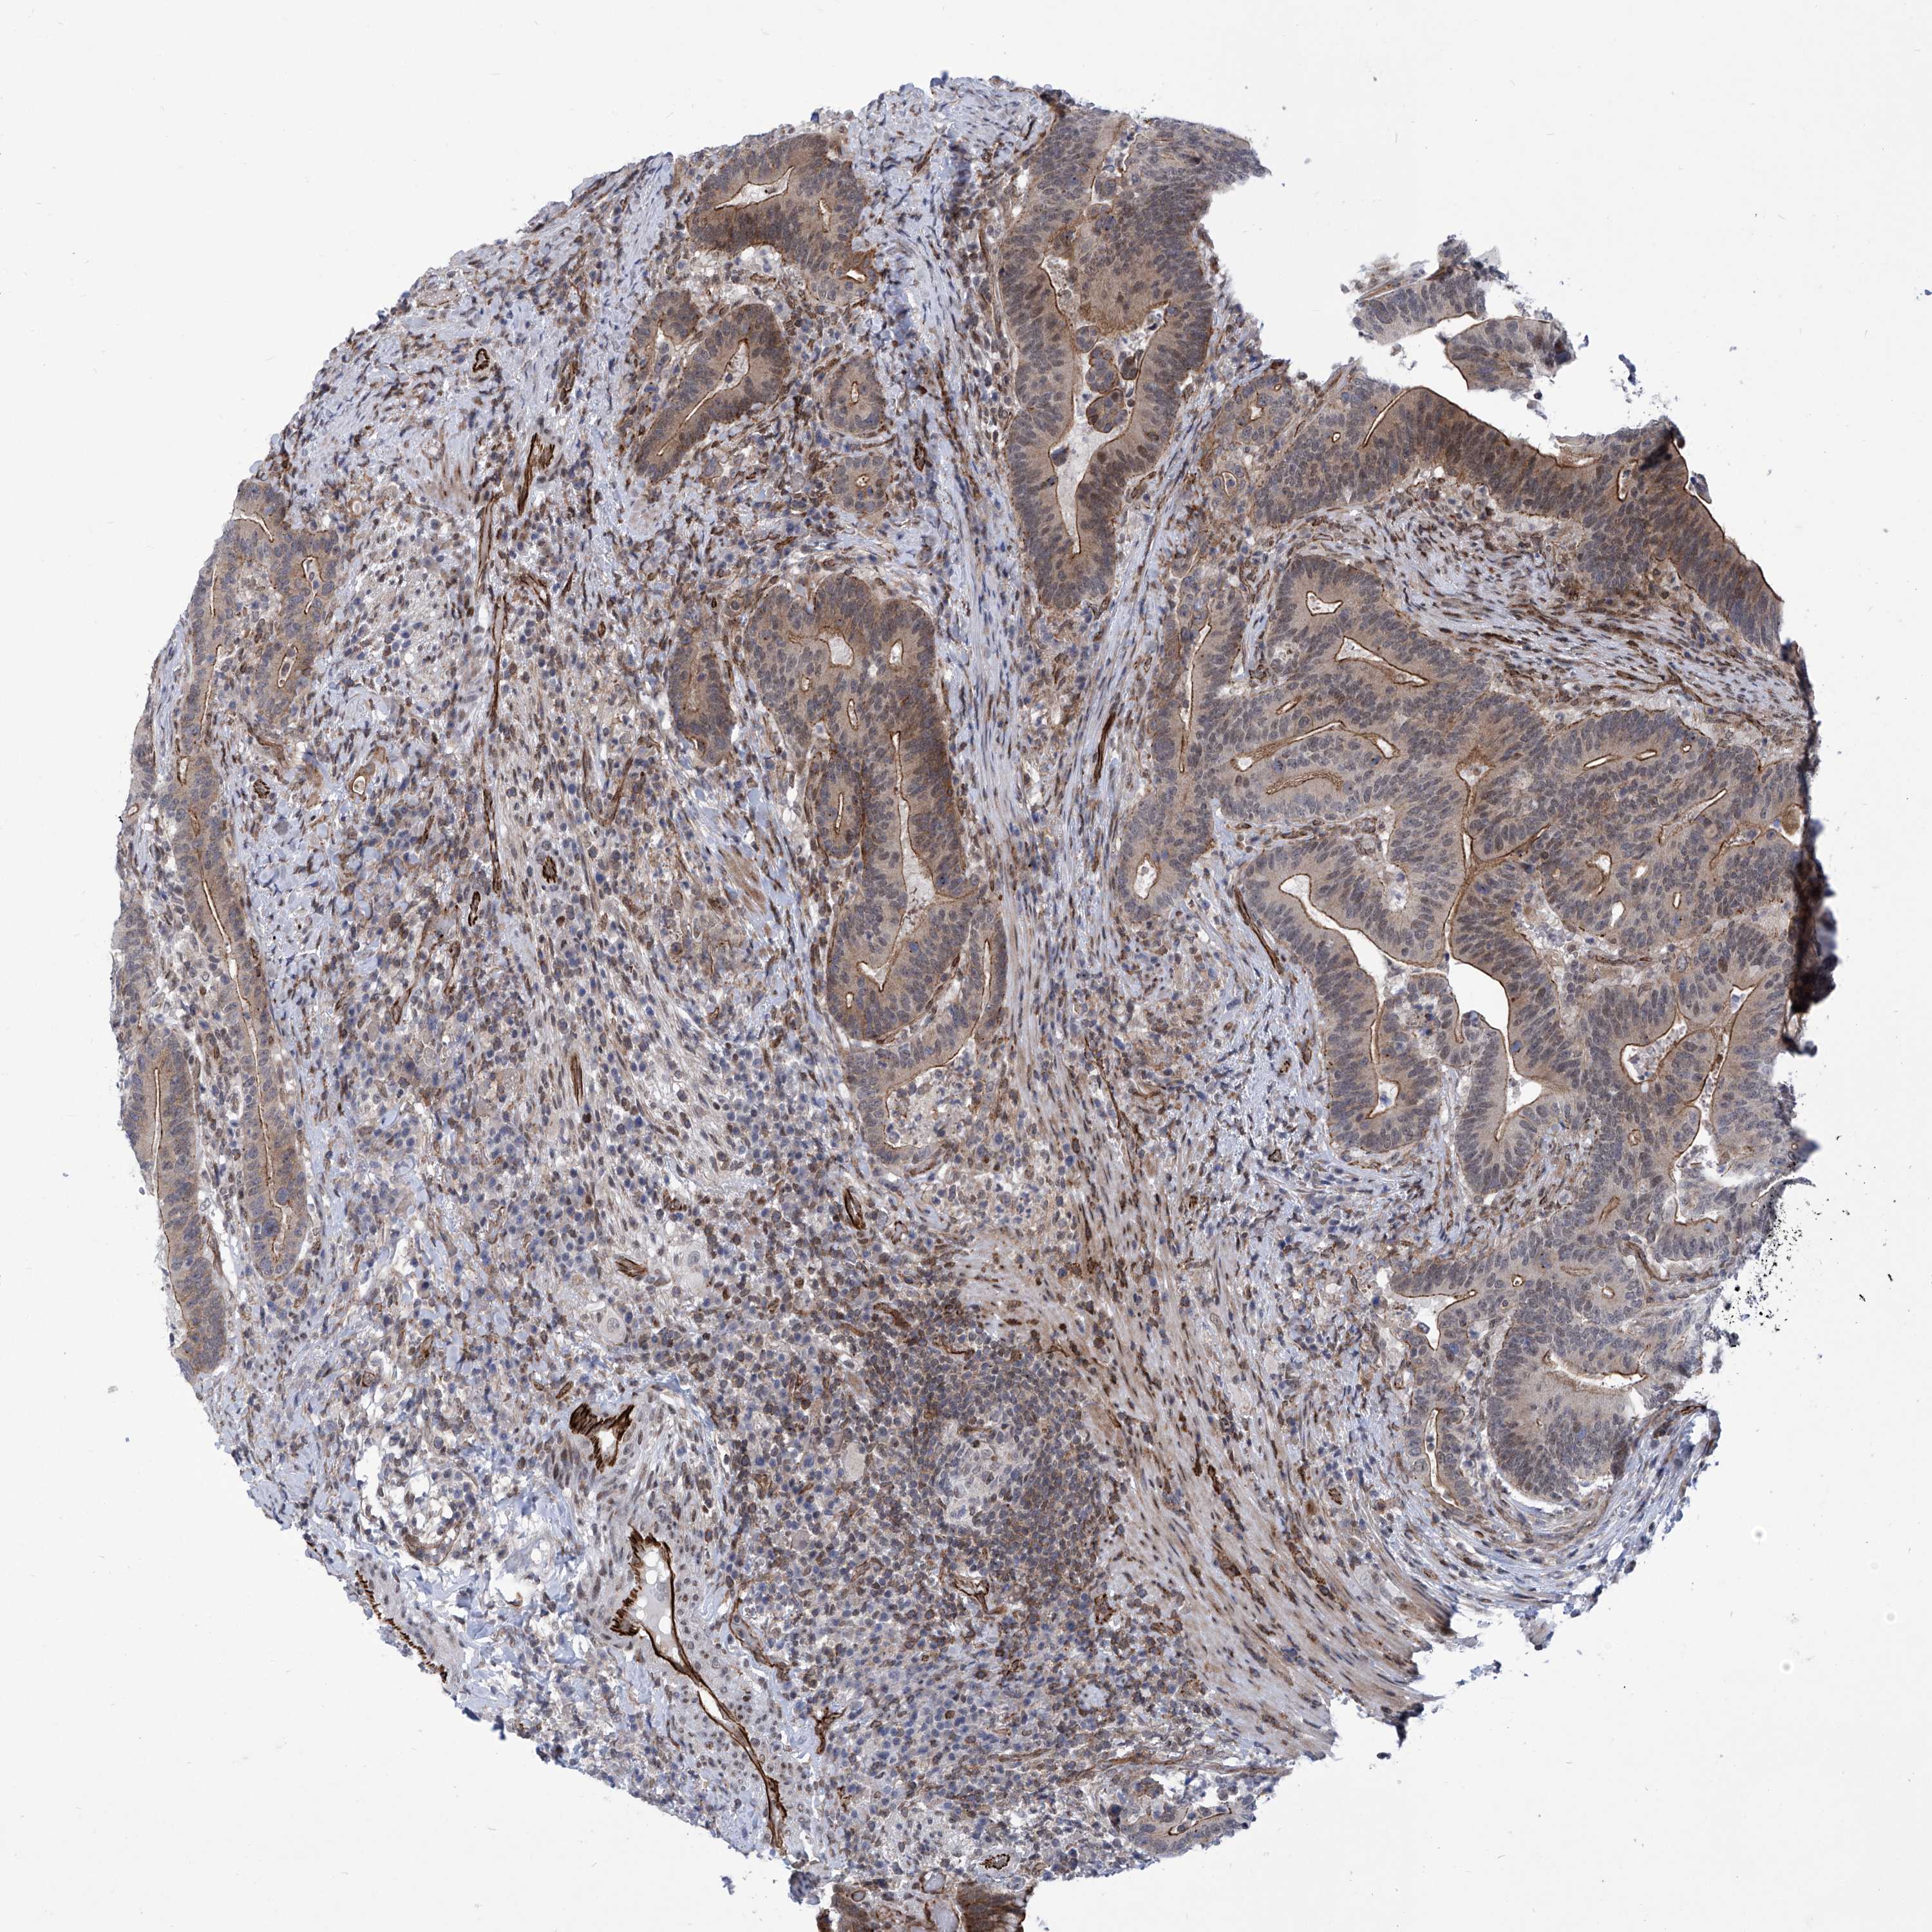

CANCER COLORECTAL CANCER Show tissue menu

Colorectal cancer

Human cancer

Colon adenocarcinoma

Rectum adenocarcinoma